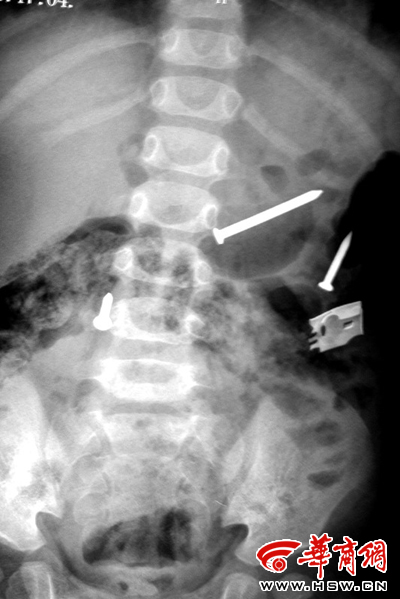

| 排出铁钉之后复检拍片又显示肚内有铁钉 |

本报榆林讯(记者 刘立春)昨晚7时许,一岁多的婷婷在病床上蹦蹦跳跳,没任何异样,但她肚子里却能“生”钉子——入院一月来,她已排泄出17枚水泥钉子,且在医院没有钉子来源,拍片显示肚内没有钉子的情况下,过不了两天,钉子会继续出现。目前她肚子里还有两根钉子和一根钢针。

5月17日,再次拍片显示婷婷的肚子里又有了三枚钉子,19日,还是三枚,且其中一个较长约5厘米。20日、21日,三枚钉子不见了,孩子的父母说,已经被排泄下来了,但是22日又出现了三枚钉子,6月2日,发现肚里有两枚。6月6日下午至7日上午排出两枚钉子和一根钢针,但昨天医院拍片子时发现,婷婷的肚子里仍有两枚钉子和一根钢针。目前,婷婷已经拍了18次片子。“如果说在家里误食了铁钉之类的东西还能说得通,但到医院后,明显拍片肚子里没有了,怎么会还有钉子或钢针,医院根本没有铁钉的来源呀!”申志军也很疑惑地说。

为防万一,目前医生已建议家长将孩子排泄出的铁钉交给医生保管。昨晚7时许,在医生办公室记者看到,孩子最后排泄出的两根铁钉和一根钢针很长,其中最长水泥钉子将近5厘米。“目前,我们不能妄加判断,只能按照误食钉子来处理。”申志军说,以前他见过吃顶针的、有吃项链的、吃玻璃球的,误食后孩子往往会身体不适,严重者可能危及生命,像婷婷这种情况他还是第一次遇到。昨日,为要验证孩子是否吃钉子,家长给钉子,孩子却不要。